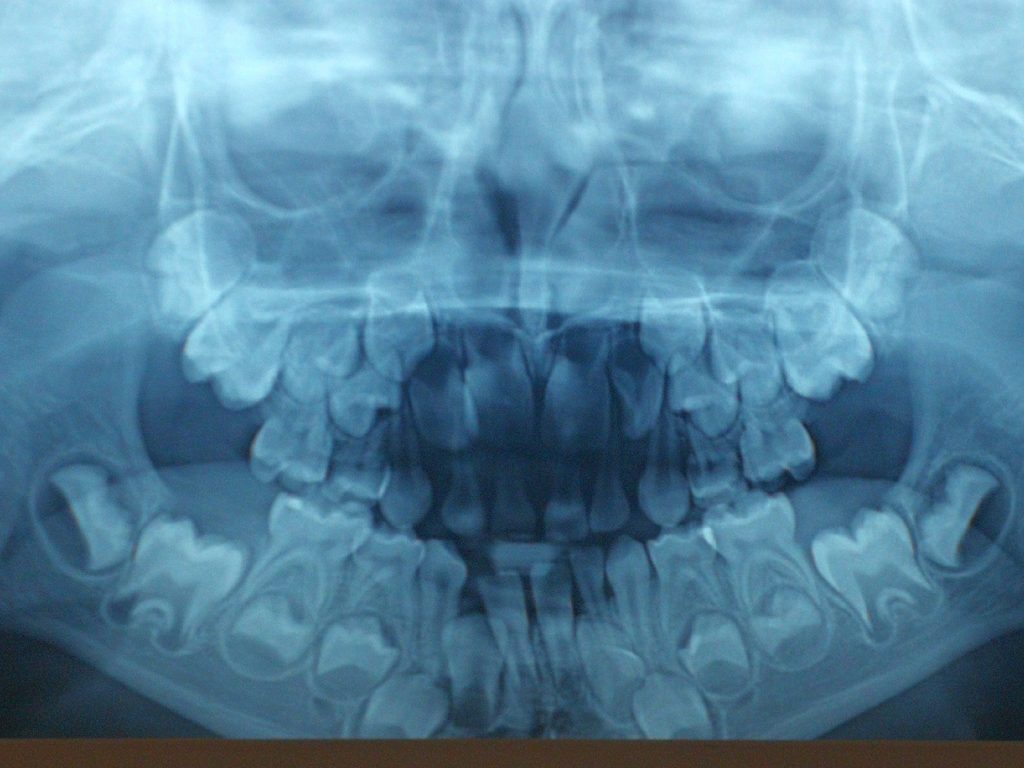

Streszczenie: Estetyka twarzy, w tym również uzębienia, jest ważnym elementem wpływającym na decyzję o podjęciu leczenia ortodontycznego przez pacjentów. Współcześnie ortodoncja z zastosowaniem nowoczesnych aparatów ortodontycznych daje duże możliwości korekty estetyki wewnątrzustnej, jak również, w razie takiej potrzeby, zewnątrzustnej u pacjenta. Dużą popularnością wśród pacjentów cieszą się aparaty stałe, dzięki którym przy dobrej współpracy pacjenta lekarz ortodonta może sprawnie przeprowadzić leczenie. Dynamiczny rozwój technologii w dziedzinie ortodoncji sprawia, że lekarz ortodonta może zaproponować swoim pacjentom nie tylko metalowe aparaty stałe. Obecnie są dostępne również: aparaty stałe estetyczne, nakładkowe i lingwalne. Leczenie ortodontyczne najczęściej jest elementem interdyscyplinarnego planu leczenia, zindywidualizowanego dla danego pacjenta. Wspólnym celem takiego leczenia jest uzyskanie optymalnej dla pacjenta harmonii, która jest kluczowa dla definiowania i postrzegania [...]